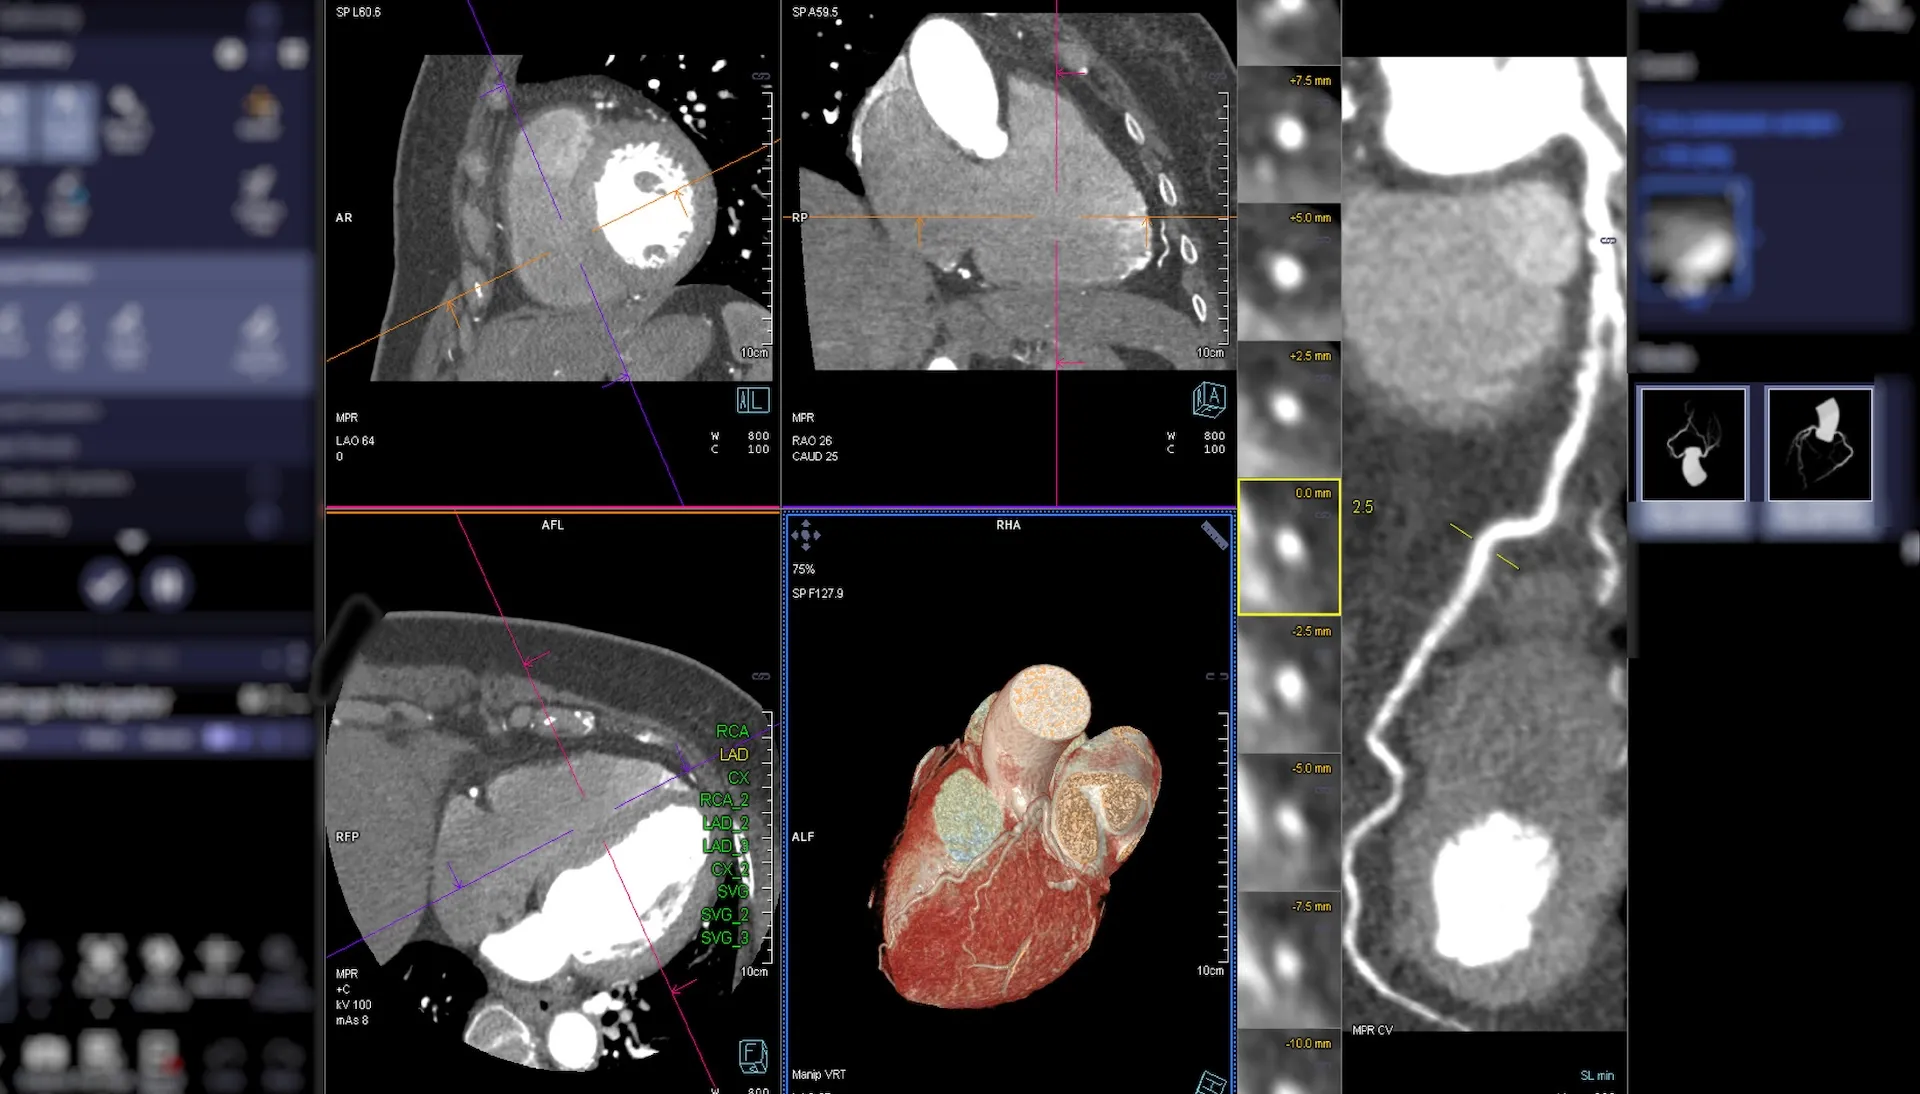

L’analyse effectuée sur l’exposition à ces contaminants a montré que, même à des niveaux considérés comme bas, il existe une corrélation avec une maladie coronarienne plus sévère. Le Dr Felipe Castillo Aravena, responsable de cette recherche, a affirmé que l’exposition prolongée à la pollution de l’air entraîne une accumulation de plaque dans les artères coronaires.

Il est à noter que les résultats diffèrent selon le genre : chez les femmes, l’exposition aux particules fines est associée à des niveaux de calcium plus élevés et à un rétrécissement plus important des artères. En revanche, chez les hommes, ce même type d’exposition montre un lien avec un accroissement du nombre de plaques dans les artères.